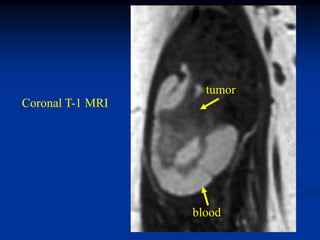

Case #263           Coronal proton density MRI

tumor

72 year female with MFH deltoid muscle

Another proton density coronal cut